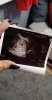

Ja po wizycie. Ciąża mlodsza. Wedlug OM 5+7 a u gin mlody 4 tydzien. Także jakos sie do was przyzwyczaiłam a termin wyjdzie raczej na lipiec. Dostalam duphaston 2x1 z racji ciut za małego progesteronu. Za dwa tygodnie mam się stawić na wizycie wtedy ma być więcej widać. Zaraz wstawie wam zdjecie pęcherzyka i ponoc mini mini kropeczki, ktorej nie widzę 🥺

Załączniki

• received_1061836204264383.jpeg

received_1061836204264383.jpeg

105,8 KB · Wyświetleń: 115

A kiedy miałaś OM? Bo zdjęcie z usg masz dokładnie takie jak ja wczoraj. Nie stresuj się, przecież nikt nie każe iść Ci na lipcowki. Możesz zostać tutaj ;) mi z OM termin wychodzi na 28.06 ale z usg będzie na bank później, A mimo to zostaje tu z wami ;)